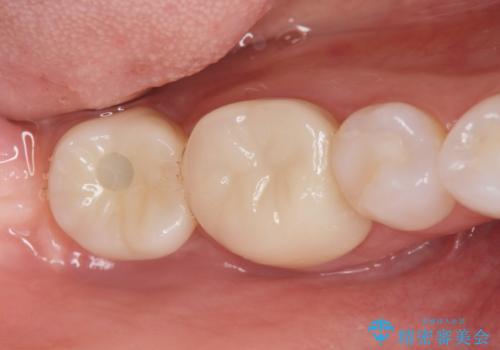

奥歯のインプラント治療

- 右下の奥歯を虫歯で喪失しそれ以来よく物が噛めず、改善を求めて来院されました。

入れ歯かインプラント治療のご提案を行い、よりしっかりとかめるインプラント治療を希望されました。

骨との結合する期間が早く、大きな咬合力にもしっかりと耐えることのできるストローマンインプラントを用いた咬合機能回復を計画します。

- 44万円(ストローマンインプラント・チタンカスタムアバットメント・仮歯・フルジルコニアクラウン)費用は治療当時の料金となります